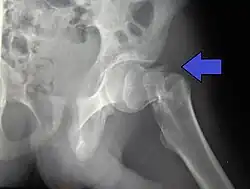

Intracapsular fractures

For low-grade fractures (Garden types 1 and 2), standard treatment is fixation of the fracture in situ with screws or a sliding screw/plate device. This treatment can also be offered for displaced fractures after the fracture has been reduced.

Fractures managed by closed reduction can possibly be treated by percutaneously inserted screws.[38]

In elderly patients with displaced or intracapsular fractures surgeons may decide to perform a hemiarthroplasty, replacing the broken part of the bone with a metal implant.[39] However, in elderly people who are medically well and still active, a total hip replacement may be indicated. Independently mobile older adults with hip fractures may benefit from a total hip replacement instead of hemiarthroplasty.[40]

Traction is contraindicated in femoral neck fractures due to it affecting blood flow to the head of the femur.[41]

The latest evidence suggests that there may be little or no difference between screws and fixed angle plates as internal fixation implants for intracapsular hip fractures in older adults.[42] The findings are based on low quality evidence that can't firmly conclude major difference in hip function, quality of life, and additional surgery.